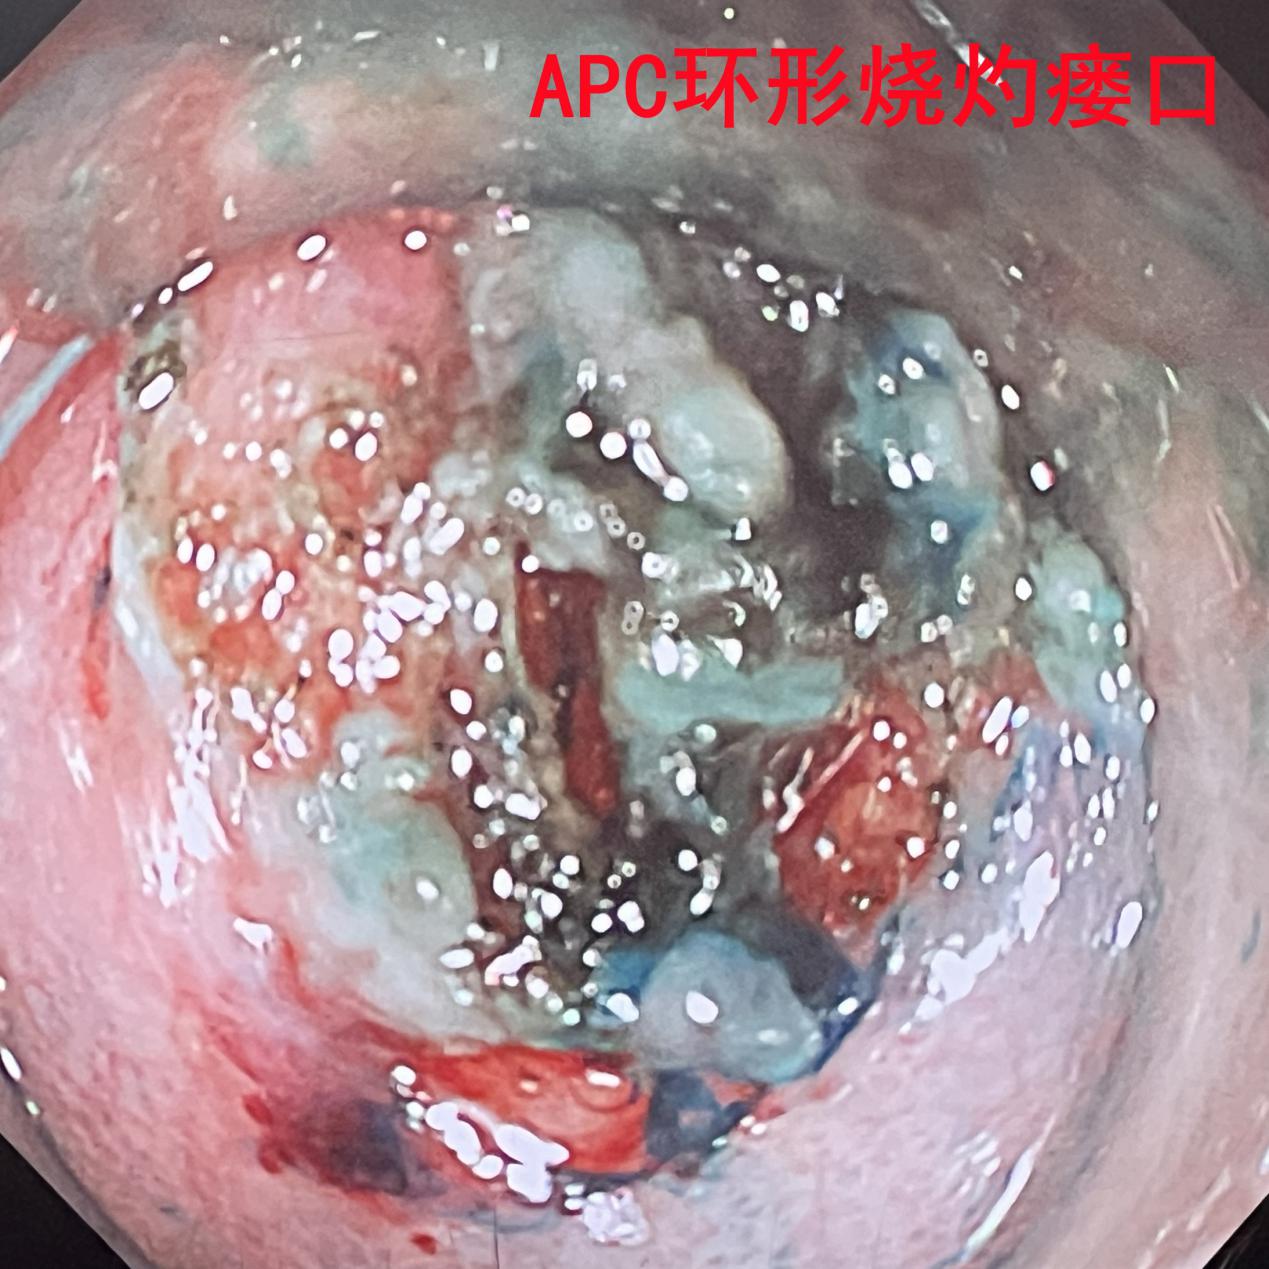

王永光教授在胃镜下,视野角度非常不利的条件下,对罪犯瘘口进行了APC环形烧灼无出血穿孔,随后使用内镜止血夹,闭合已经凝切后的瘘孔以封堵食管-右上支气管瘘的食管侧,手术获得圆满成功。